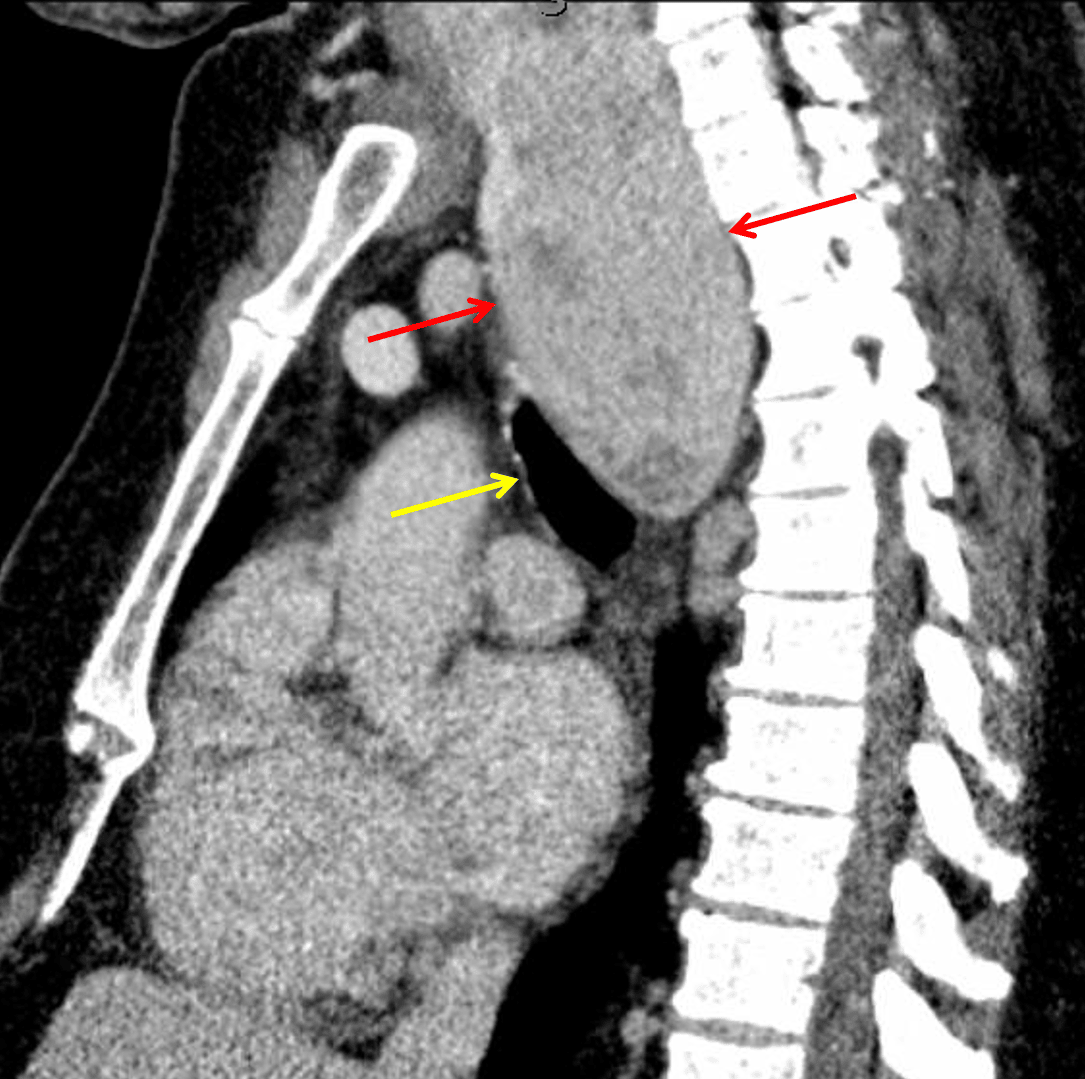

Large thyroid goiter extending inferiorly as a posterior mediastinal mass (red arrows) with mass effect on the trachea (yellow arrow).

• Large right posterior mediastinal mass measuring 10 cm in craniocaudal span with mass effect on the trachea

Posterior mediastinal mass (thyroid goiter)